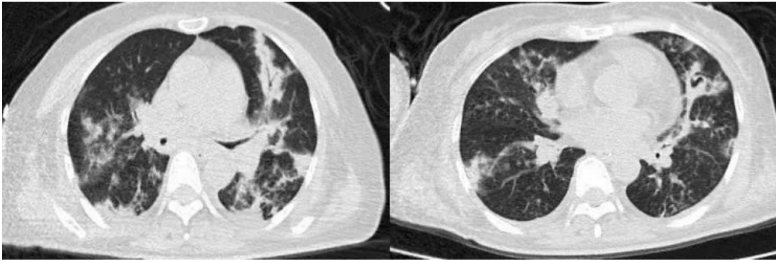

患者男性,51岁,因“咳嗽、咳痰5天,发热伴呼吸困难3天”入院。入院前曾应用静脉激素。既往有胰腺癌病史,入院后发现血糖明显升高,并确诊2型糖尿病。乙型流感病毒核酸阳性。血清GM试验阴性,BALF GM >5 S/CO,曲霉IgG阴性,BALF mNGS提示烟曲霉(序列数809975),乙型流感病毒(序列数2732),BALF培养结果为烟曲霉,对伏立康唑耐药。患者胸部CT及气管镜结果如下图所示。患者,男性,36岁,因“咳嗽、咳痰1周,呼吸困难2天”入院。入院前2天外院诊断糖尿病酮症酸中毒、乙型流感病毒性肺炎,并有使用静脉激素。入院查乙型流感病毒核酸阳性。BALF GM>5 S/CO,血清GM 4.8 S/CO,曲霉IgG阴性,BALF mNGS提示烟曲霉(序列数25173),乙型流感病毒(序列数90),气道假膜钳夹组织及BALF培养烟曲霉。患者胸部CT及气管镜结果如下图所示。IAPA的发病率较高,且在不同的流感亚型中无显著差异。而且IAPA的病死率高,但早期临床表现缺乏特异性,诊断存在一定困难,应引起临床医师的高度关注。早期、准确地识别与诊断IAPA,及时启动抗真菌治疗是改善预后的关键。[1] Iuliano AD, Roguski KM, Chang HH, et al. Estimates of global seasonal influenza‑associated respiratory mortality: a modelling study[J]. Lancet, 2018, 391(10127):1285-1300. [2] Verweij PE, Rijnders BJA, Brüggemann RJM, et al. Review of influenza‑associated pulmonary aspergillosis in ICU patients and proposal for a case definition: an expert opinion[J]. Intensive Care Med, 2020, 46(8): 1524-1535.[3] Martin-Loeches I, J Schultz M, Vincent JL, et al. Increased incidence of co-infection in critically ill patients with influenza[J]. Intensive Care Med, 2017, 43(1):48-58.[4] ABBOTT JD, FERNANDO HV, GURLING K, et al. Pulmonary aspergillosis following post‑influenzal bronchopneumonia treated with antibiotics[J]. Br Med J, 1952, 1(4757):523-525. [5] Martin-Loeches I, J Schultz M, Vincent JL, et al. Increased incidence of coinfection in critically ill patients with influenza[J]. Intensive Care Med, 2017, 43:48-58.[6] Schauwvlieghe AFAD, Rijnders BJA, Philips N, et al. Invasive aspergillosis in patients admitted to the intensive care unit with severe influenza: a retrospective cohort study[J]. Lancet Respir Med, 2018, 6(10): 782-792.[7] Beumer MC, Koch RM, van Beuningen D, et al. Influenza virus and factors that are associated with ICU admission, pulmonary co-infections and ICU mortality[J]. J Crit Care, 2019, 50:59-65. [8] Huang L, Zhang N, Huang X, et al. Invasive pulmonary aspergillosis in patients with influenza infection: a retrospective study and review of the literature[J]. Clin Respir J, 2019, 13(4):202-211. [9] Krifors A, Blennow O, Påhlman LI, et al. Influenza-associated invasive aspergillosis in patients admitted to the intensive care unit in Sweden: a prospective multicentre cohort study[J]. Infect Dis (Lond), 2024, 56(2):110-115.[10] Lu LY, Lee HM, Burke A, et al. Prevalence, Risk Factors, Clinical Features, and Outcome of Influenza-Associated Pulmonary Aspergillosis in Critically Ill Patients: A Systematic Review and Meta-Analysis[J]. Chest, 2024, 165(3):540-558. [11] Delaney JW, Pinto R, Long J, Lamontagne F, et al. The influence of corticosteroid treatment on the outcome of influenza A (H1N1pdm09)‑related critical illness[J]. Crit Care, 2016, 20:75.[12] [Nedel WL, Nora DG, Salluh JI, et al. Corticosteroids for severe influenza pneumonia: A critical appraisal[J]. World J Crit Care Med, 2016, 5(1):89-95.[13] Wauters J, Baar I, Meersseman P, et al. Invasivepulmonary aspergillosis is a frequent complication of critically ill H1N1 patients: a retrospective study[J]. Intensive Care Med, 2012, 38(11):1761-1768.[14] Rodriguez-Goncer I, Thomas S, Foden P, et al. Invasive pulmonary aspergillosis is associated with adverse clinical outcomes in critically ill patients receiving veno‑venous extracorporeal membrane oxygenation[J]. Eur J Clin Microbiol Infect Dis, 2018, 37(7):1251-1257. [15] Cavayas YA, Yusuff H, Porter R. Fungal infections in adult patients on extracorporeal life support[J]. Crit Care, 2018, 22(1):98. [16] Clancy CJ, Nguyen MH. Acute community-acquired pneumonia due to Aspergillus in presumably immunocompetent hosts: clues for recognition of a rare but fatal disease[J]. Chest, 1998, 114:629-634.[17] Hasejima N, Yamato K, Takezawa S, et al. Invasive pulmonary aspergillosis associated with influenza B[J]. Respirology, 2005;10:116-119.[18] van de Sandt CE, Bodewes R, Rimmelzwaan GF, et al, Rimmelzwaan GF, de Vries RD. Influenza B viruses: not to be discounted[J]. Future Microbiol, 2015, 10(9):1447-1465. [19] Matias G, Taylor R, Haguinet F, et al. Estimates of mortality attributable to influenza and RSV in the United States during 1997-2009 by influenza type or subtype, age, cause of death, and risk status[J]. Influenza Other Respir Viruses, 2014, 8(5):507-515.[20] Kuek LE, Lee RJ. First contact: the role of respiratory cilia in host-pathogen interactions in the airways[J]. Am J Physiol Lung Cell Mol Physiol, 2020, 319(4):L603-L619.[21] Ghoneim HE, Thomas PG, McCullers JA. Depletion of alveolar macrophages during influenza infection facilitates bacterial superinfections[J]. J Immunol, 2013, 191(3):1250-1259.[22] Fox A, Le NM, Horby P, et al. Severe pandemic H1N1 2009 infection is associated with transient NK and T deficiency and aberrant CD8 responses[J]. PLoS One, 2012, 7(2):e31535.[23] Short KR, et al. Pathogenesis of influenza induced acute respiratory distress syndrome. Lancet Infect Dis. 2014;14(1): 57-69.[24] Dewi IM, et al. Neuraminidase and SIGLEC15 modulate the host defense against pulmonary aspergillosis. Cell Rep Med. 2021;2(5): 100289.[25] Ohta H, Yamazaki S, Miura Y, et al. Invasive tracheobronchial aspergillosis progressing from bronchial to diffuse lung parenchymal lesions[J]. Respirol Case Rep, 2016, 4(1):32-34.[26] Saha BK, Chong W. A 61-Year-Old Man With Influenza Pneumonia and New Onset Hemoptysis[J]. Chest, 2021, 160(2):e181-e184.[27] 罗丹心, 谷林, 阎锡新. 体外膜肺氧合治疗重症流感相关肺曲霉病1例并文献复习[J]. 国际呼吸杂志, 2023, 43(4):448-453.[28] Park DW, Yhi JY, Koo G, et al. Fatal clinical course of probable invasive pulmonary aspergillosis with influenza B infection in an immunocompetent patient[J]. Tuberc Respir Dis (Seoul), 2014, 77(3):141-144.[29] Meersseman W, Vandecasteele SJ, Wilmer A, et al. Invasive aspergillosis in critically ill patients without malignancy[J]. Am J Respir Crit Care Med, 2004, 170(6):621-625.[30] Lahmer T, Neuenhahn M, Held J, et al. Comparison of 1,3-β-dglucan with galactomannan in serum and bronchoalveolar fluid for the detection of Aspergillus species in immunosuppressed mechanical ventilated critically ill patients[J]. J Crit Care, 2016, 36:259-264.[31] Zhu N, Zhou D, Xiong W, et al. Performance of mNGS in bronchoalveolar lavage fluid for the diagnosis of invasive pulmonary aspergillosis in non-neutropenic patients[J]. Front Cell Infect Microbiol, 2023, 13:1271853.[32] Patterson TF, Thompson GR 3rd, Denning DW, et al. Practice Guidelines for the Diagnosis and Management of Aspergillosis: 2016 Update by the Infectious Diseases Society of America[J]. Clin Infect Dis, 2016, 63(4):e1-e60. [33] Ullmann AJ, Aguado JM, Arikan-Akdagli S, et al. Diagnosis and management of Aspergillus diseases: executive summary of the 2017 ESCMID-ECMM-ERS guideline[J]. Clin Microbiol Infect, 2018, 24 Suppl 1:e1-e38. [34] Lu Y, Liu L, Li H, et al. The clinical value of Aspergillus-specific IgG antibody test in the diagnosis of nonneutropenic invasive pulmonary aspergillosis[J]. Clin Microbiol Infect, 2023, 29(6):797.e1-797.e7. [35] Donnelly JP, Chen SC, Kauffman CA, et al. Revision and Update of the Consensus Definitions of Invasive Fungal Disease From the European Organization for Research and Treatment of Cancer and the Mycoses Study Group Education and Research Consortium[J]. Clin Infect Dis, 2020, 71(6):1367-1376.[36] Springer J, White PL, Hamilton S, et al. Comparison of performance characteristics of Aspergillus PCR in testing a range of blood-based samples in accordance with international methodological recommendations[J]. J Clin Microbiol, 2016, 54(3):705-711.[37] Eigl S, Hoenigl M, Spiess B, et al. Galactomannan testing and Aspergillus PCR in same-day bronchoalveolar lavage and blood samples for diagnosis of invasive aspergillosis[J]. Med Mycol, 2017, 55(5):528-534.[38] Mengoli C, Cruciani M, Barnes RA, et al. Use of PCR for diagnosis of invasive aspergillosis: systematic review and meta-analysis[J]. Lancet Infect Dis, 2009, 9(2):89-96.[39] Springer J, Lackner M, Nachbaur D, et al. Prospective multicentre PCR-based Aspergillus DNA screening in high-risk patients with and without primary antifungal mould prophylaxis[J]. Clin Microbiol Infect, 2016, 22(1):80-86.[40] 施毅, 赵江南. 侵袭性真菌病病原学非培养实验室诊断方法[J]. 中华结核和呼吸杂志, 2019, 42(7):500-505[41] Eigl S, Prattes J, Lackner M, et al. Multicenter evaluation of a lateral-flow device test for diagnosing invasive pulmonary aspergillosis in ICU patients[J]. Crit Care, 2015, 19(1):178.[42] Jenks JD, Mehta SR, Taplitz R, et al. Point-of-care diagnosis of invasive aspergillosis in non-neutropenic patients: aspergillus galactomannan lateral flow assay versus aspergillus-specific lateral flow device test in bronchoalveolar lavage[J]. Mycoses, 2019, 62(3):230-236.[43] Maertens JA, Raad II, Marr KA, et al. Isavuconazole versus voriconazole for primary treatment of invasive mould disease caused by Aspergillus and other filamentous fungi (SECURE): a phase 3, randomised-controlled, non-inferiority trial[J]. Lancet, 2016, 387(10020):760-769.[44] Maertens JA, Rahav G, Lee DG, et al. Posaconazole versus voriconazole for primary treatment of invasive aspergillosis: a phase 3, randomised, controlled, non-inferiority trial[J]. The Lancet, 2021, 397(10273):499-509.[45] Thompson 3rd GR, Soriano A, Cornely OA, et al. Rezafungin versus caspofungin for treatment of candidaemia and invasive candidiasis (ReSTORE): a multicentre, double-blind, double-dummy, randomised phase 3 trial[J]. Lancet, 2023, 401(10370):49-59.[46] Shaw KJ, Ibrahim AS. Fosmanogepix: A Review of the First-in-Class Broad Spectrum Agent for the Treatment of Invasive Fungal Infections[j]. J Fungi (Basel), 2020, 6(4):239. [47] Petraitis V, Petraitiene R, Katragkou A, et al. Combination Therapy with Ibrexafungerp (Formerly SCY-078), a First-in-Class Triterpenoid Inhibitor of (1→3)-β-d-Glucan Synthesis, and Isavuconazole for Treatment of Experimental Invasive Pulmonary Aspergillosis[J]. Antimicrob Agents Chemother, 2020, 64(6):e02429-19.[48] Wiederhold NP. Review of the Novel Investigational Antifungal Olorofim[J]. J Fungi (Basel), 2020, 6(3):122. [49] Zhou M, Liu L, Cong Z, et al. A dual-targeting antifungal is effective against multidrug-resistant human fungal pathogens[J]. Nat Microbiol, 2024, 9(5):1325-1339.